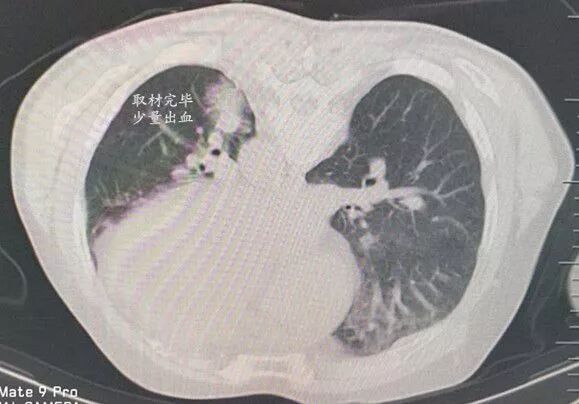

肺窗示左肺下葉背段脊柱旁一最大徑約12mm軟組織結節(jié)

俯臥位時靶病灶空間位置稍有變化,距皮60mm,僅占據一個CT層面,橫徑僅比相鄰的左肺下靜脈略大,且完全被后肋遮擋。

采用頭腳縱軸成角入路沿下位肋間隙斜上方向置入導針,CT顯示導針進入肺內,左右、頭腳方向準確,已達靶病灶邊緣。

沿導針方向順利置入16G活檢槍,CT顯示正中靶心,激發(fā)取材,

穿刺完畢復掃CT僅有少量肺內針道滲血,無需處理。